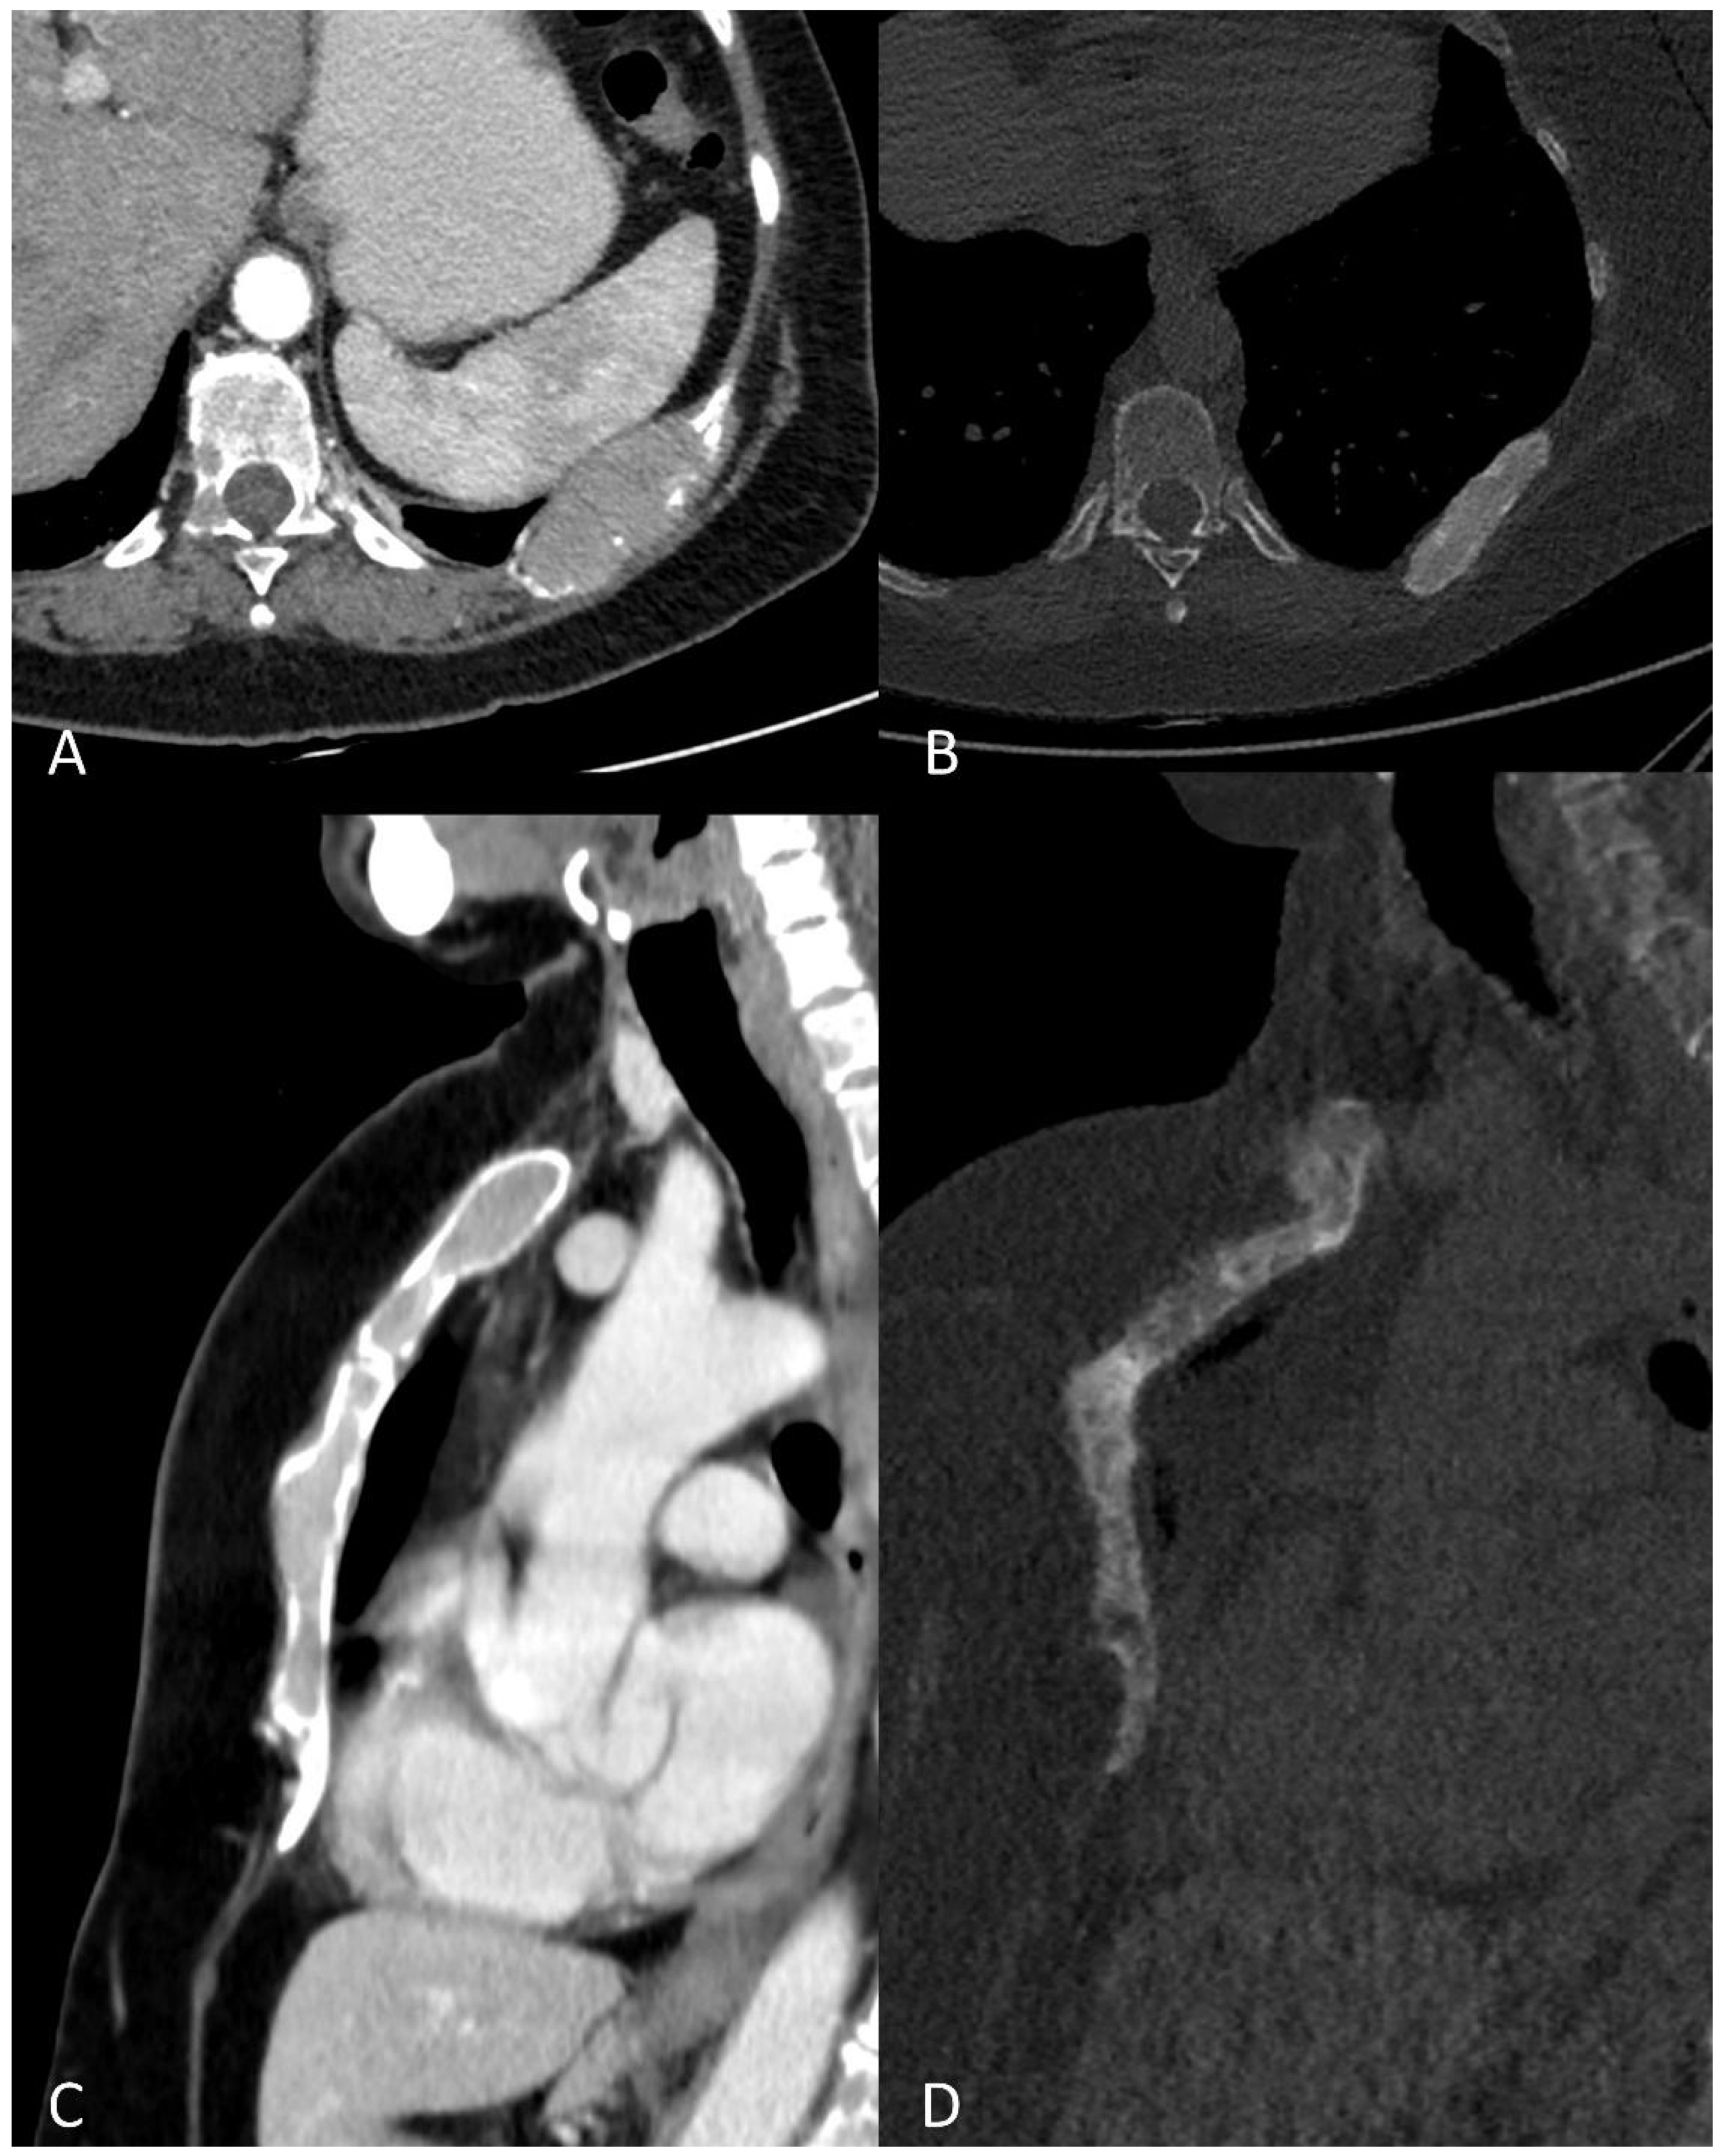

Whole-Body Low-Dose Multidetector-Row CT in Multiple Myeloma: Guidance in Performing, Observing, and Interpreting the Imaging Findings

3. WBLD-CT Imaging Findings and Evaluation